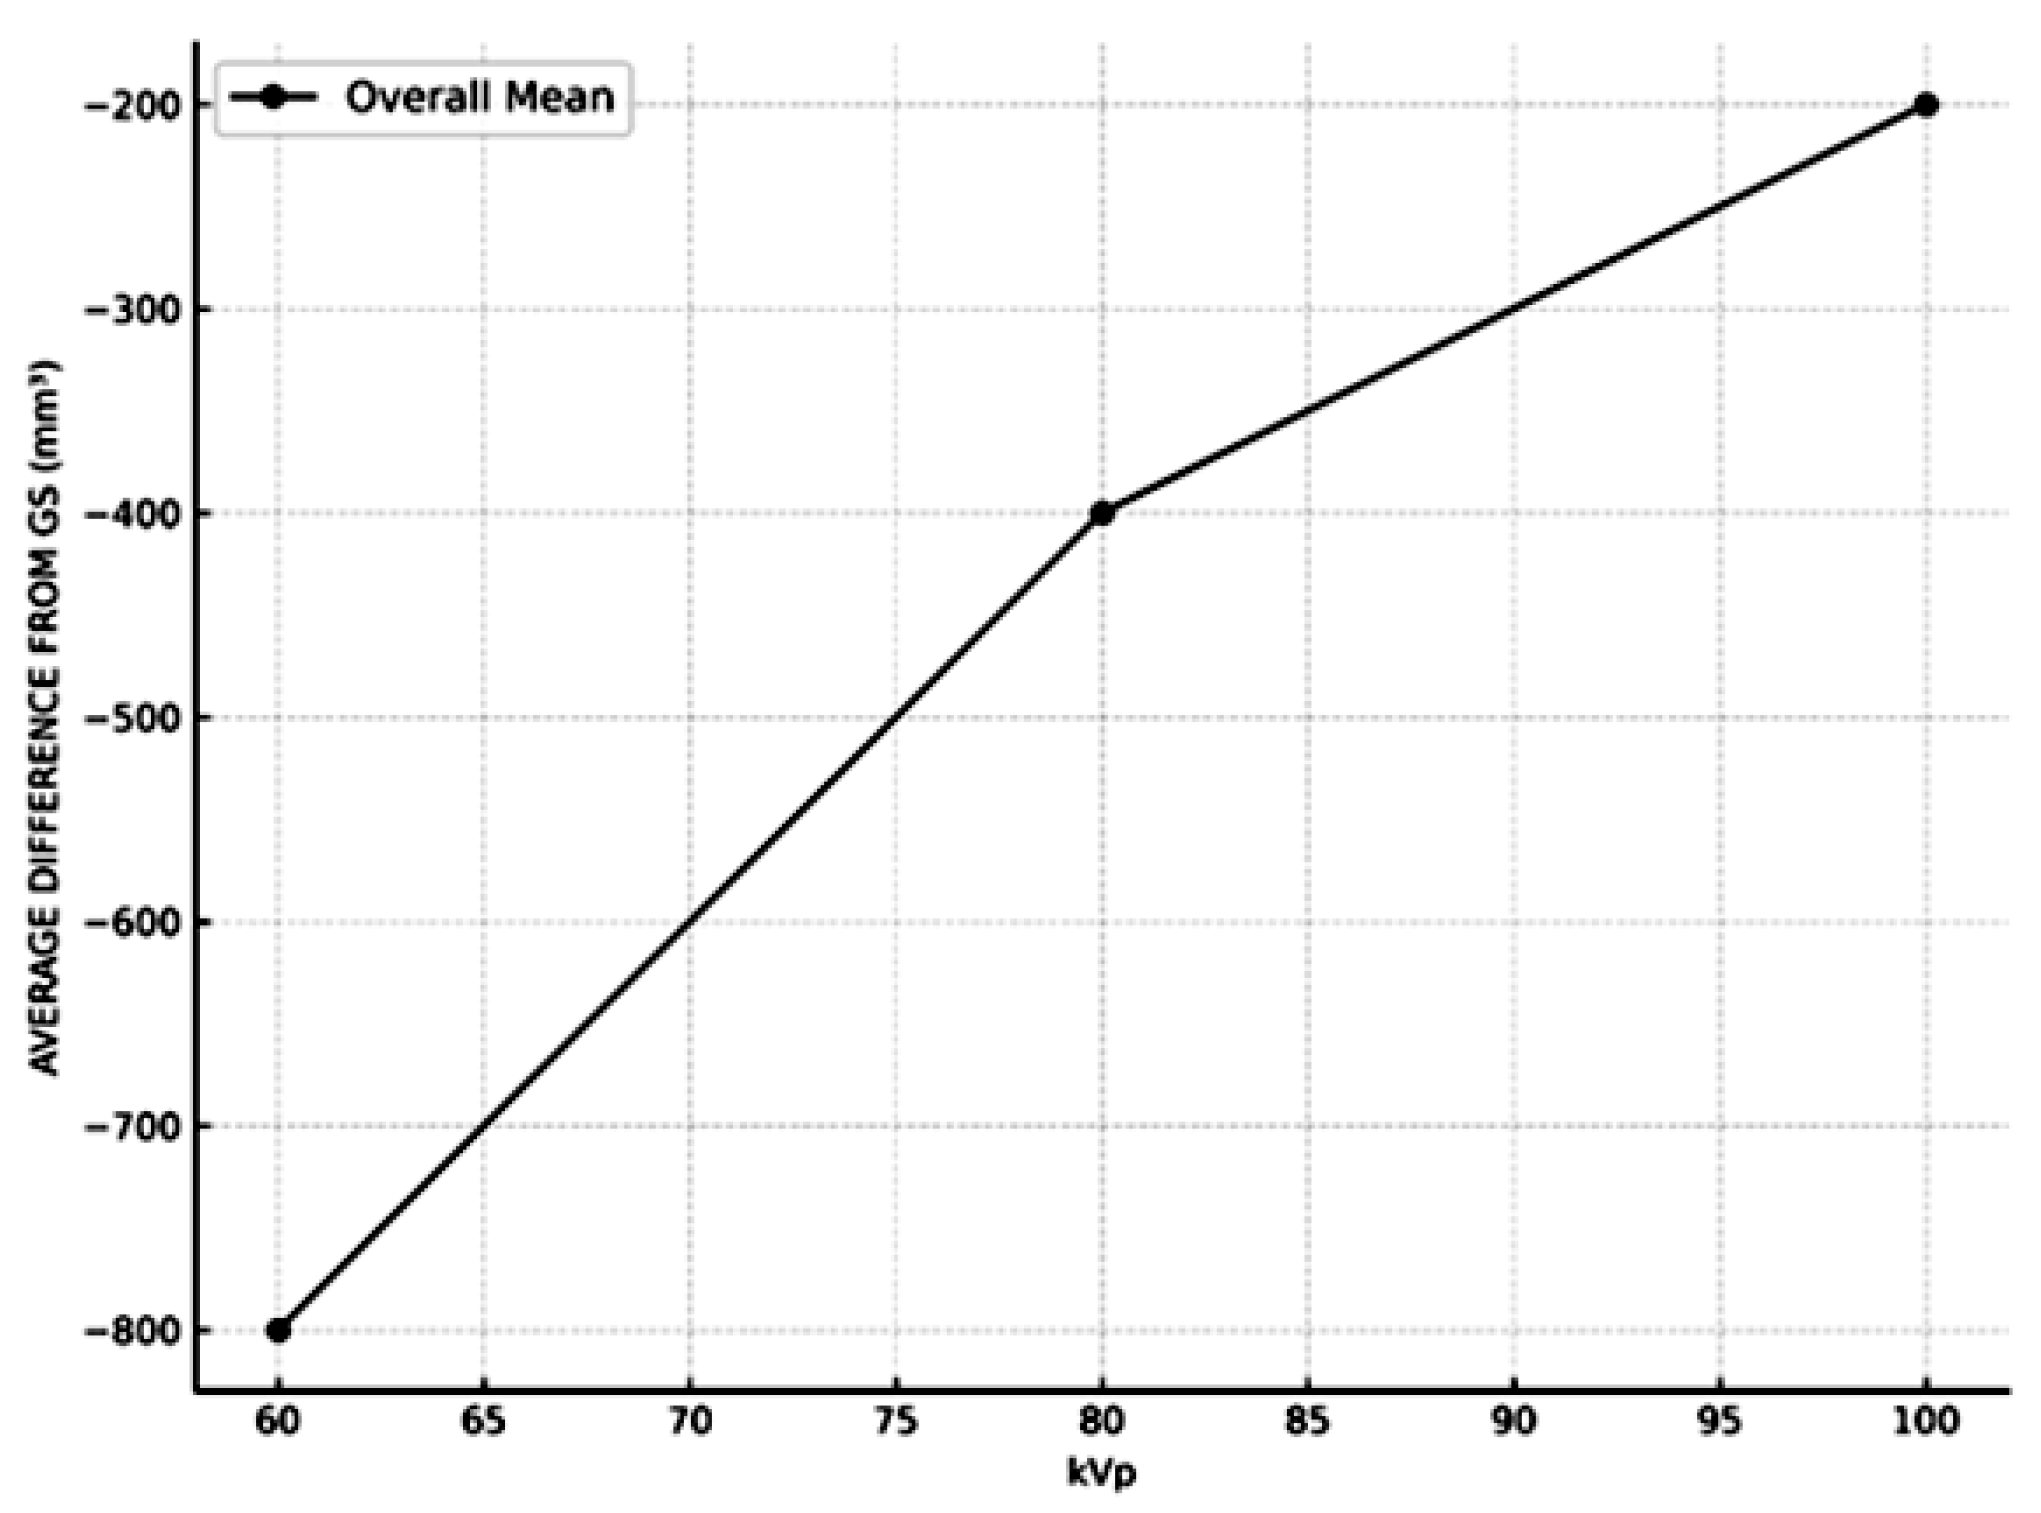

3. Results

- kVp settings had a significant effect on measurement accuracy, with higher kVp levels yielding results closer to the GS.